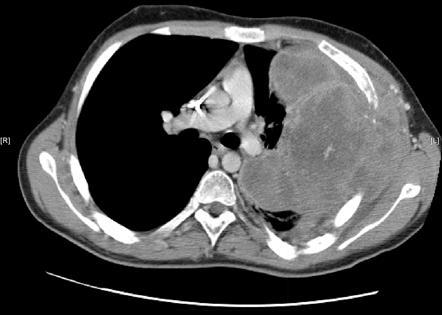

43yo F with SLE presents with dyspnea

Pericardial Effusion

cardiac shadow is enlarged but the pulmonary vessels are not dilated –> suspect a pericardial effusion.

azygous vein and SVC may be dilated, reflecting the elevated central venous pressure necessary to maintain right ventricular filling.

mediastinal interface over the left hilum in the absence of enlargement of the pulmonary arteries should also alert you to possibility of a pericardial effusion (fluid accumulating in a pericardial recess) because an enlarged cardiac chamber, such as the left atrial appendage, will not produce an interface this high along the left cardiac border.